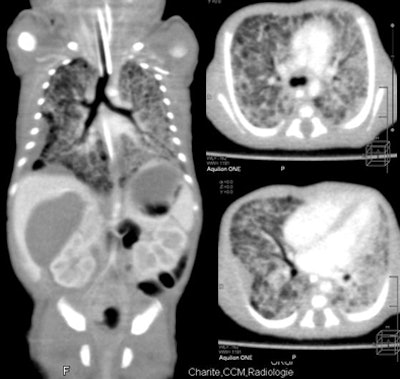

| Feeding artery is visible at 320-detector-row CT in a patient with pulmonary blastoma. |